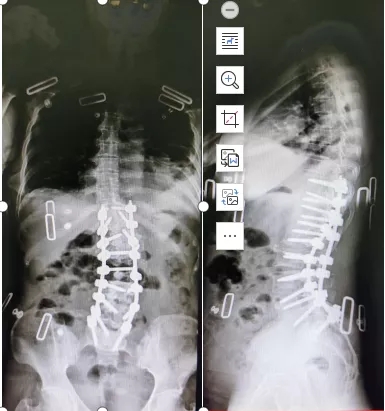

医生和患者详细沟通后,患者最终选择了胸腰椎后路滑脱复位、减压、侧凸矫形手术。

患者手术后影像

在麻醉科、ICU 和专业神经监护全力配合下,脊柱、骨病外科手术团队为患者顺利地完成了手术,术后患者顺利出院,术后复查随访恢复良好,生活质量得到了很大提高。